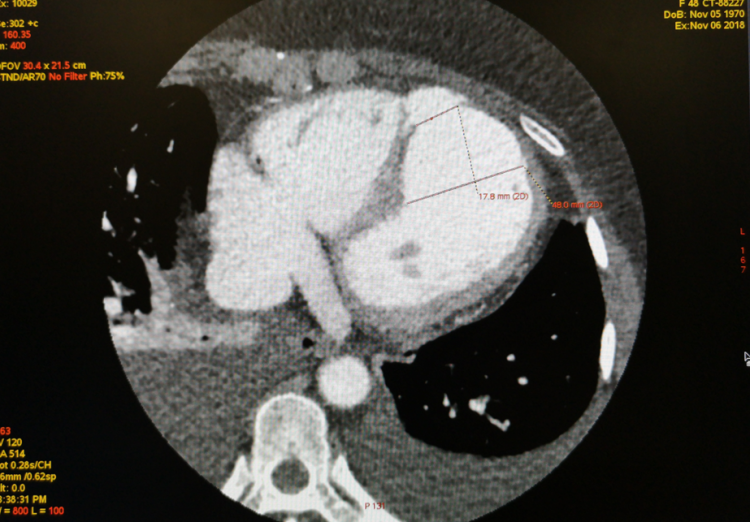

首例会诊患者因“急诊PCI术后冠脉急性闭塞、室壁瘤形成、室间隔穿孔”于11月5日从外院转入我院治疗,住院第二天即心衰症状加重急行IABP植入术。患者各项指标经治疗后逐渐好转,但检查发现其再发心梗、室间隔穿孔明显扩大。考虑到患者病情较为复杂,手术存在较大风险,为保障患者安全和医疗质量,经医院内病例讨论决定紧急邀请阜外医院专家提供技术支持,并顺利在我院ICU连线完成远程多学科疑难病例会诊讨论。